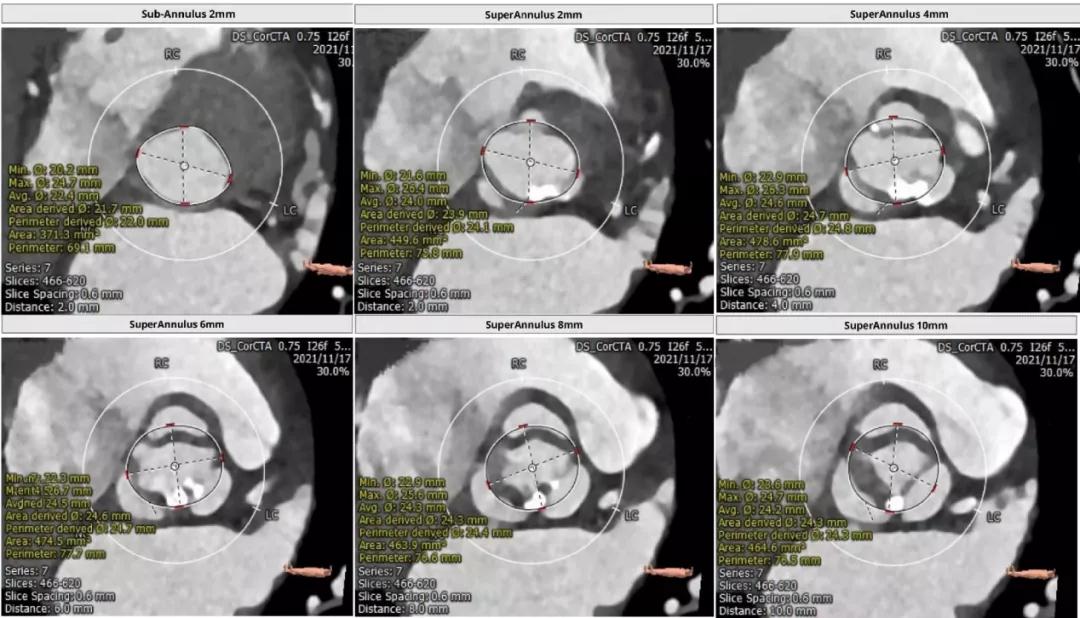

主动脉瓣CT评估:

三叶瓣,瓣环直径22.4mm,瓣环长短径分别为25.0*20.0mm,周长为70.4mm,面积为383.4mm²。左室流出道直径21.8mm,瓦式窦31.7mm*30.2mm*30.6mm,左冠高度11.1mm,右冠高度15.3mm,窦管交界直径26.3mm。

瓣上多平面测量:

根部解剖: